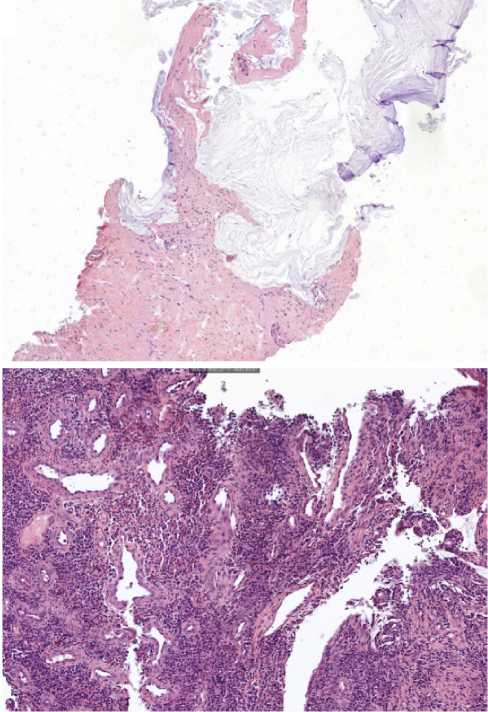

Помимо этого, пациенту проведена видеоколоноскопия: в просвете верхнеампулярного отдела прямой кишки сохраняется стенозирующая опухоль (рис. 11). По результатам гистологического исследования биоптатов опухолевых клеток не выявлено, фрагменты грануляционной ткани с участками слизистой оболочки толстой кишки (рис. 12).

Рис. 11. Результаты видеоколоноскопиии на фоне иммунотерапии пембролизумабом у пациента 38 лет с диагнозом метастатический колоректальный рак с признаками микросателлитной нестабильности; по данным трепан-биопсии опухолевых клеток не обнаружено (10 января 2024 г.)

Fig. 11. Results of video colonoscopy during immunotherapy with pembrolizumab in a 38-year-old patient diagnosed with metastatic MSI-H colorectal cancer; no tumour cells were detected after trephine biopsy (10 January 2024)

Рис. 12. Результаты морфологического исследования: а - препарат печени (×200), б-препарат кишки (×20) на фоне 14 введений иммунотерапии пембролизумабом у пациента 38 лет с диагнозом метастатический колоректальный рак с признаками микросателлитной нестабильности; опухолевых клеток не выявлено

Fig. 12. Results of morphological examination: a - liver preparation (×200), b - intestine preparation (×20) against the background of 14 infusions of pembrolizumab immunotherapy in a 38-year-old patient diagnosed with metastatic MSI-H colorectal cancer; tumor cells were not detected